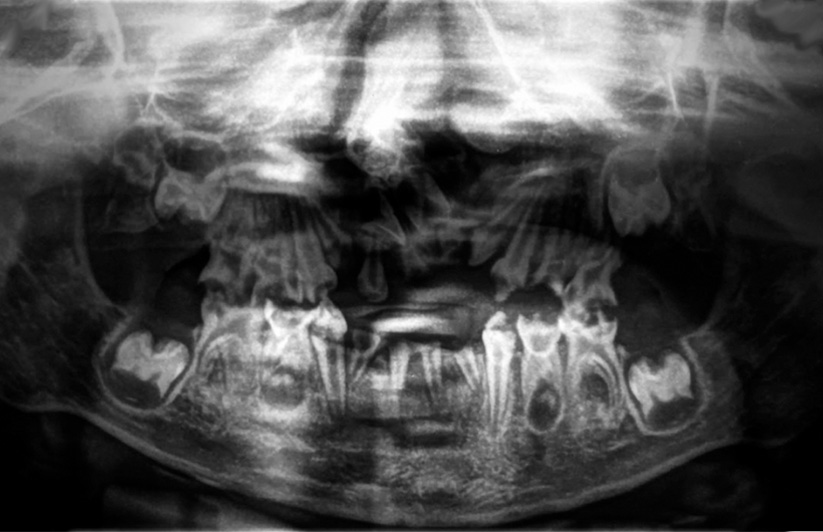

El tratamiento odontológico inicial consistió en la toma de radiografías periapicales de los cuatro cuadrantes, al igual que dos radiografías oclusales oblicuas, superior e inferior, respectivamente (figura 3 A, B, C, D, E y F), y una radiografía panorámica (figura 4). Se realizó interconsulta con el pediatra de cabecera explicando el diagnóstico obtenido de la revisión clínica y radiográfica, con el fin de conseguir la autorización para el procedimiento bajo anestesia general.

Figura 4. Radiografía panorámica.